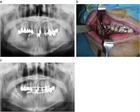

1. 顎顔面外傷は、交通事故、転倒、転落、スポーツ、殴打など種々な原因で生じるもので、 受傷部位により顔面の軟組織損傷(顔面皮膚や口腔粘膜の損傷)、歯および歯周組織損傷(歯の破折、脱臼)、顎顔面骨損傷(上顎骨や下顎骨などの骨折)に大別される。